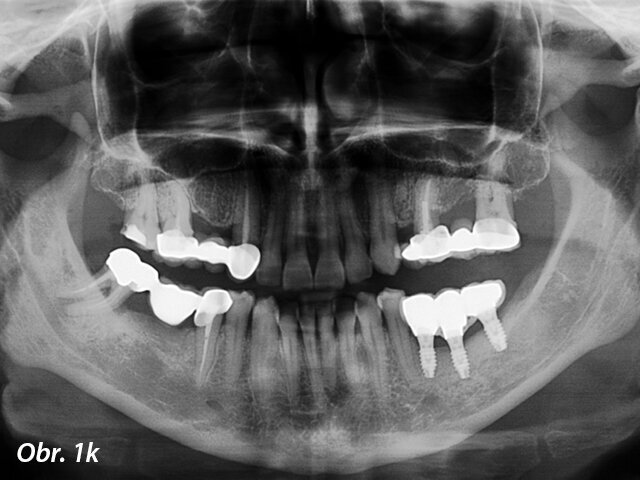

Pacient s dehiscencí ošetřený pomocí GBR s nezanořeným postupem: a) Předoperační panoramatický rentgenový snímek, b) Předoperační pohled na okluzi, c) Atrofie kosti alveolárního hřebene vizualizovaná po odklopení laloku, d) Zavedení implantátů do oblasti 35, 36 a 37, e) Syntetická kost překrývající dehiscenci, f) Resorbovatelná membrána aplikovaná přes kostní náhradu, g) Sutury, h) Zhojené měkké tkáně, i) Okluzální pohled na umístěnou protetickou práci, j) Laterální pohled na protetickou práci

Panoramatický rentgenový snímek jeden rok od zatížení